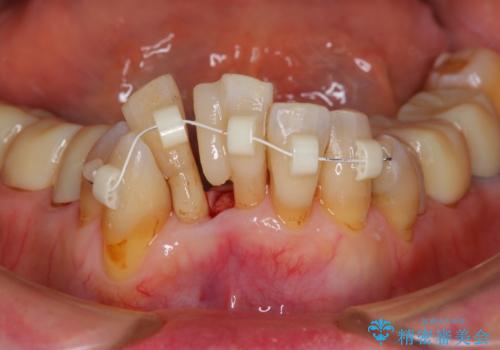

- 上顎前歯の黒ずみの改善、下顎前歯の十度なガタつき、矯正治療とセラミック治療を含む全体的な治療を希望され来院されました。

銀歯を高強度の仮歯に替えたのち、下顎前歯のみの部分矯正→全体的なマウスピース矯正治療(インビザライン)→最終的なセラミック治療と治療を進めます。